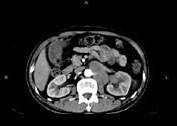

问题 男,65岁,左腰部隐痛不适2个月,CT平扫+增强如图所示,下列说法正确的是 ( )

选项 A、考虑为左肾癌伴肾门淋巴结转移 B、增强扫描可见左肾局部隆起左肾内的病灶强化方式相同 C、腹腔内未见积液,所示骨质亦未见破坏 D、平扫时可见左肾局部隆起,腹主动脉旁、肾门部有等密度的块影

答案 ABCD